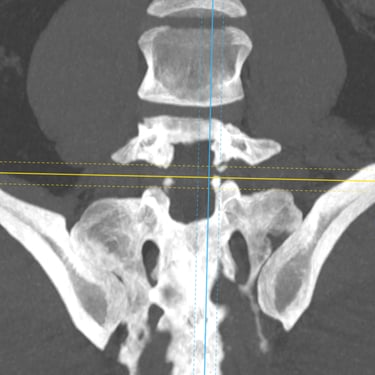

Listesis Lumbar L5–S1 por Fractura Ístmica: Estabilización con FTP y TLIF

La listesis lumbar L5–S1 por fractura ístmica se produce por un defecto en la pars interarticularis que genera inestabilidad vertebral, dolor lumbar crónico y compromiso radicular. Cuando el tratamiento conservador no es efectivo, la artrodesis lumbar con fijación transpedicular (FTP) asociada a la fusión intersomática transforaminal (TLIF) es una alternativa quirúrgica eficaz. Este procedimiento permite descomprimir las raíces nerviosas, restaurar la alineación vertebral y lograr una fijación sólida del segmento afectado. La combinación de estabilización y fusión reduce el dolor, mejora la función y favorece una recuperación segura y progresiva.